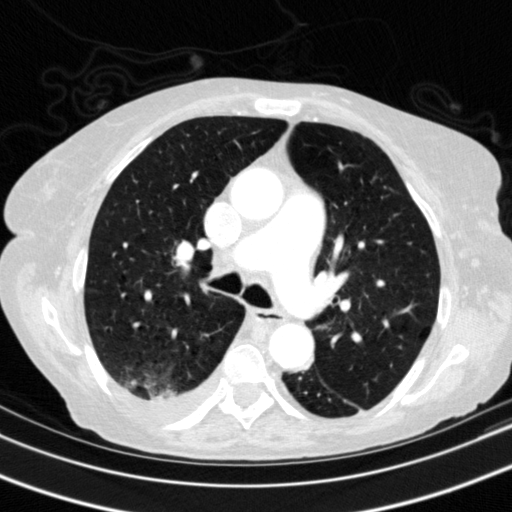

Targeted Slice 70 - Lung Window Analysis (Generated vs Real Venous)

0.598

Lung SSIM

162.3

Lung RMSE

72.3

Lung MAE

Average Lung Window Metrics Across All Slices (153 slices) - Generated vs Real Venous

0.579

Lung SSIM (Avg)

146.5

Lung RMSE (Avg)

66.3

Lung MAE (Avg)

Generated VENOUS CT scan (A→B translation)

Lung window (WL -600, WW 1500 β†’ Low βˆ’1350, High +150)